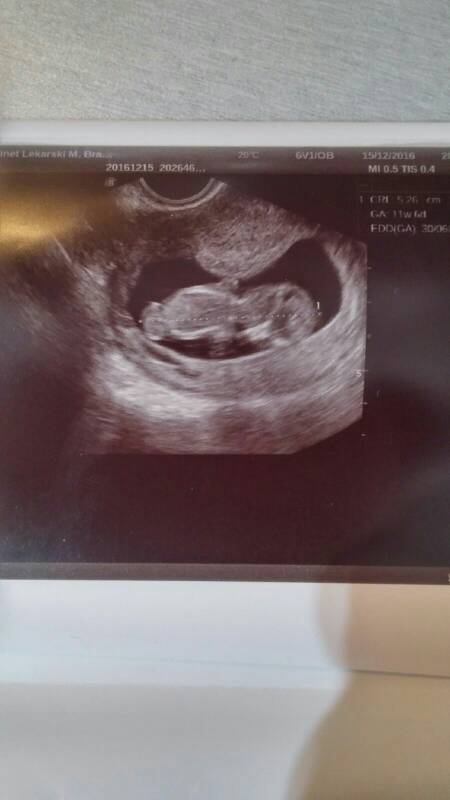

Zobacz załącznik 787647 Justyna gratuluję, my staraliśmy się wcześniej o syna ponad 7 lat więc wiem jaka to radość.

To moje szczęście.

6 cm, noga prawie 2 cm, obwód główki ponad 7,7cm haha.

Zdjęcie mało wyraźne niestety..

Między nogami nic a nic nje było.. A siedziało jakby na głowicy.

Karoo śliczne zdjęcie!

Jak NT??